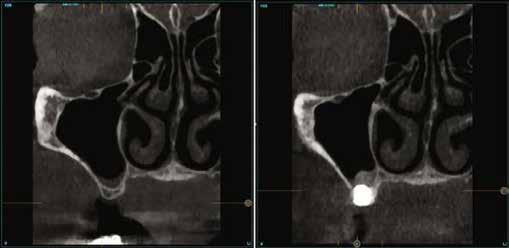

A CT metszetekben a 48-as gyökerei körbeölelik a canalis mandibularist, amelyet piros nyíllal jelöltünk a fotókon.

Szeretnék mutatni néhány ábrát az egyik bonyolult esetről, a közelmúltból. A CT-n látszik, hogy a három gyökér teljesen „körbenőtte” az ideget. Van olyan frontális metszeti kép, ahol csak a gyökerek vannak a nervus körül, ezen a szakaszon egyáltalán nincs meg a csontos fala a canalisnak. Szeparációs technikával, viszonylag könnyen, minimális traumával, szövődménymentesen sikerült eltávolítani a fog minden részét. A várakozásnak megfelelően, a beteg nem számolt be paraesthesiáról.